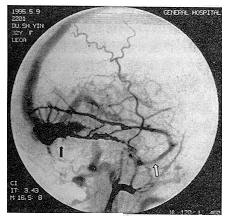

摘要 目的:报告27例侧窦型硬脑膜动脉瘘(DAVF),对其发病机理、血供与临床的关系以及治疗方法的选择进行探讨。方法:25例病人行血管内栓塞治疗,2例栓塞结合手术治疗。结果:解剖愈合18例,好转6例,2例无效,1例术后死于肺炎。结论:作者认为,临床表现与静脉引流类型密切相关,头痛和耳后杂音是最常见的发病症状;全脑血管造影是确诊和研究本病唯一可靠的手段;对以颈外动脉及锁骨下动脉分支供血为主者,选择性血管内栓塞治疗是安全、有效、首选的治疗方法。对颈内动脉和椎动脉脑膜支参与供血者,则以血管内栓塞结合手术治疗为宜。

Abstract Objective: To report 27 cases ofdural arteriovenous fistulae (DAVF) of the lateral sinus. The pathogenesis, relationshipbetween blood supply and clinical presentation, and the choice of treatment were discussed. Methods: The treatment modalities were endovascular embolization alone (25 cases) andembolizations followed by surgery (2 cases). Results: There were complete anatomical curein 18 cases, angiographic improvement in 6 cases, no effect in 2 cases and one died ofpostoperative pneumonia. Conclusion: The authors believes that the clinical presentationschiefly depend on the type of venous drainage of DAVF. The most common symptoms wereheadache and auricular noises. Cerebral angiography was the most valuable means indiagnosing and investigating of the DAVF. Endovascular embolization was a safe andeffective method in breating the fistulae fed by branches of the external carotid arteryand subclavian artery. Endovascular embolization followed by surgery was a better methodin treatment of the fistalae fed by meningeal branches of the internal carotid artery andvertebral artery.